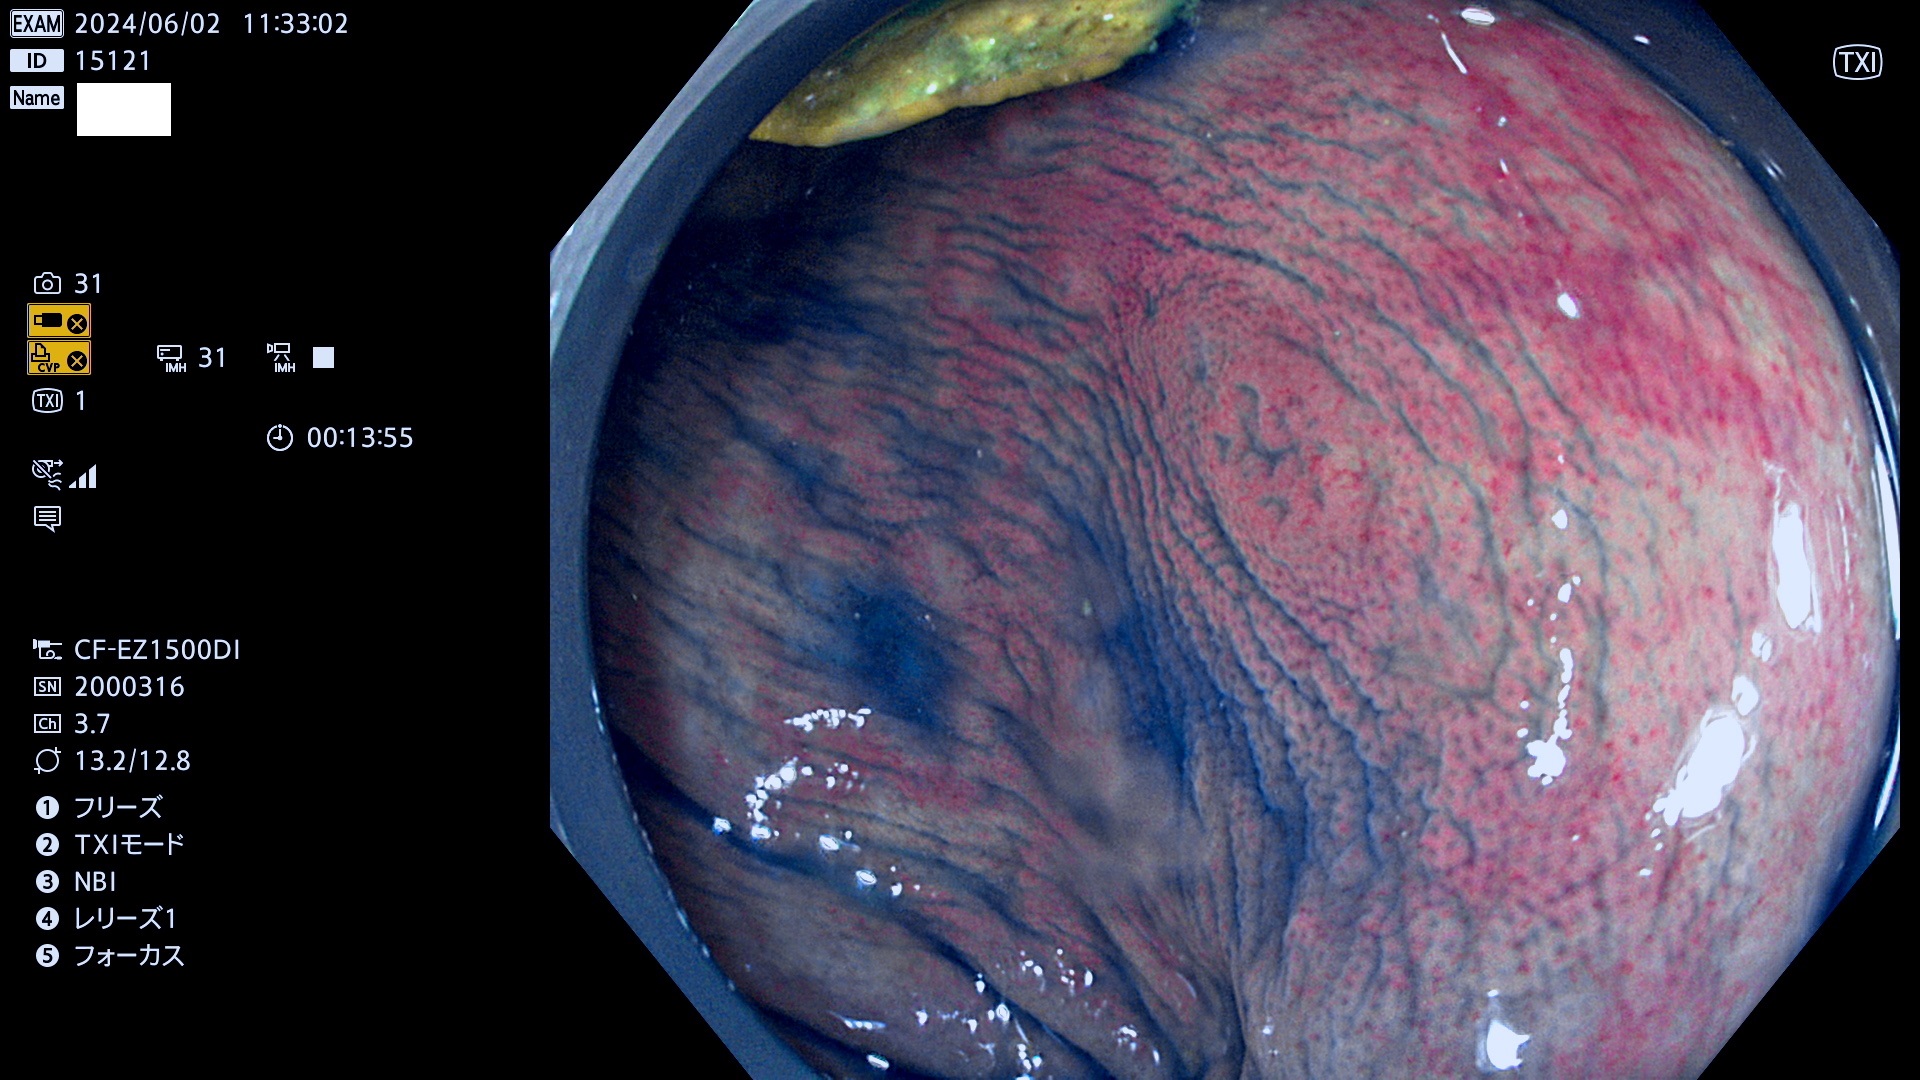

今週のUb、Uc型腺腫

表面型腺腫(Flat Adenoma)の中で、完全に平坦な物をUb、陥凹している物をUcと呼びます。平坦隆起型(Ua)よりも、発見が難しく危険な病変です。

毎週の検査(木・金・土・日)に発見されたUb、Uc型・腺腫を、その週の日曜の夜にUPし1週間、提示します。

抽出の対象期間 2024年5月30日〜6月2の4日間(40件の検査)7件 (7/40=18%)